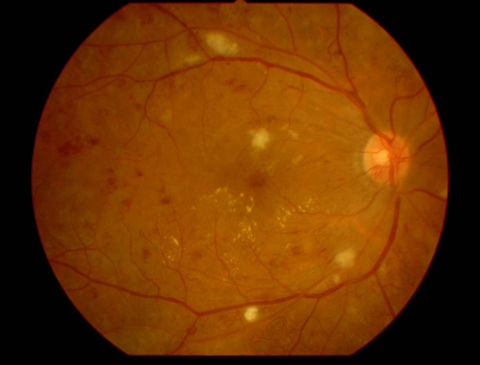

2.前増殖糖尿病網膜症

| 病期 | 症状 | 治療法 |

|---|---|---|

| 中期の網膜症 | 毛細血管がつまり血管閉塞を生じます。血管閉塞した網膜は虚血におちいり、軟性白斑という所見が生じます。 | 虚血網膜は放置することによって、新生血管が生じ、硝子体出血や増殖膜のもとになるため、この段階で、的確なレーザー治療(網膜光凝固術)をしっかりと行っておくことが非常に重要になります。 |

軟性白斑 |